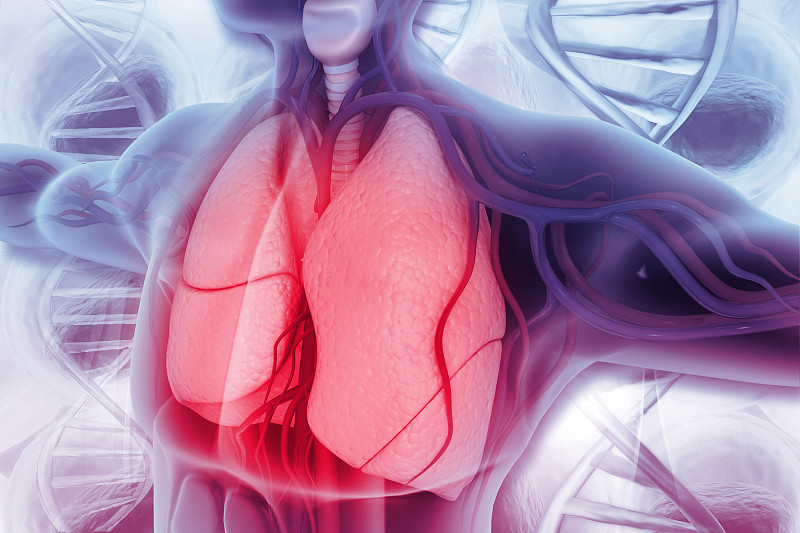

人类肺部的科学背景详情

JPG